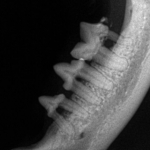

Feline dental radiograph demonstrating periodontal diseaseRegular professional cleaning is important to maintaining your pet’s teeth. We use a modern and safe ultrasonic scaler to clean each tooth thoroughly–above and below the gum line. We perform comprehensive dental charting. Our advanced dental care also includes digital dental radiology and extractions.